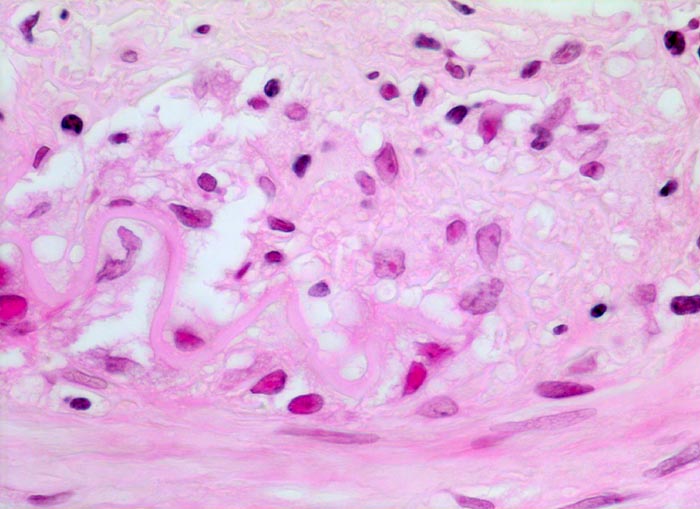

Histologisch diagnostisch ist der Nachweis von monohistiozytären Entzündungsinfiltraten entlang der Lamina elastica interna und deren Fragmentierung bzw. Zerstörung über längere Strecken (> 242). In frischen Läsionen findet sich die Entzündung unter Umständen ausschliesslich im Bereich der Vasa vasorum der Adventitia und der Media. In nur 50% der Fälle sind mehrkernige Riesenzellen (> 237) vorhanden. Seltenere Befunde sind eine Entzündung der Vasa vasorum, Verkalkungen der Lamina elastica, Intimaverdickungen und fibrinoide Gefässwandnekrosen. In Abwesenheit einer Entzündung lässt sich eine abgeheilte Arteritis temporalis nicht von atherosklerotischen oder unspezifischen altersbedingten Veränderungen der Arterie unterscheiden.

• Arteriensegment mit dichten, zirkulären lymphohistioplasmazellulären Entzündungsinfiltraten mit Beteiligung neutrophiler Granulozyten in allen Wandschichten (Adventitia, Media und Intima).

• Histiozyten und mehrkernige Riesenzellen finden sich bevorzugt entlang der Lamina elastica interna. Die Riesenzellen enthalten teilweise phagozytierte Fragmente der Lamina elastica interna.

• Fragmentierung, Abblassung und herdförmig Zerstörung der Lamina elastica interna über längere Strecken (EvG Färbung).

• Ausgeprägte Intimafibrose mit mit dichten Infiltraten zerfallender neutrophiler Granulozyten.

• Das Gefässlumen partiell obliterierender frischer Gerinnungsthrombus. Das sollte der Kliniker dem Pathologen mitteilen: